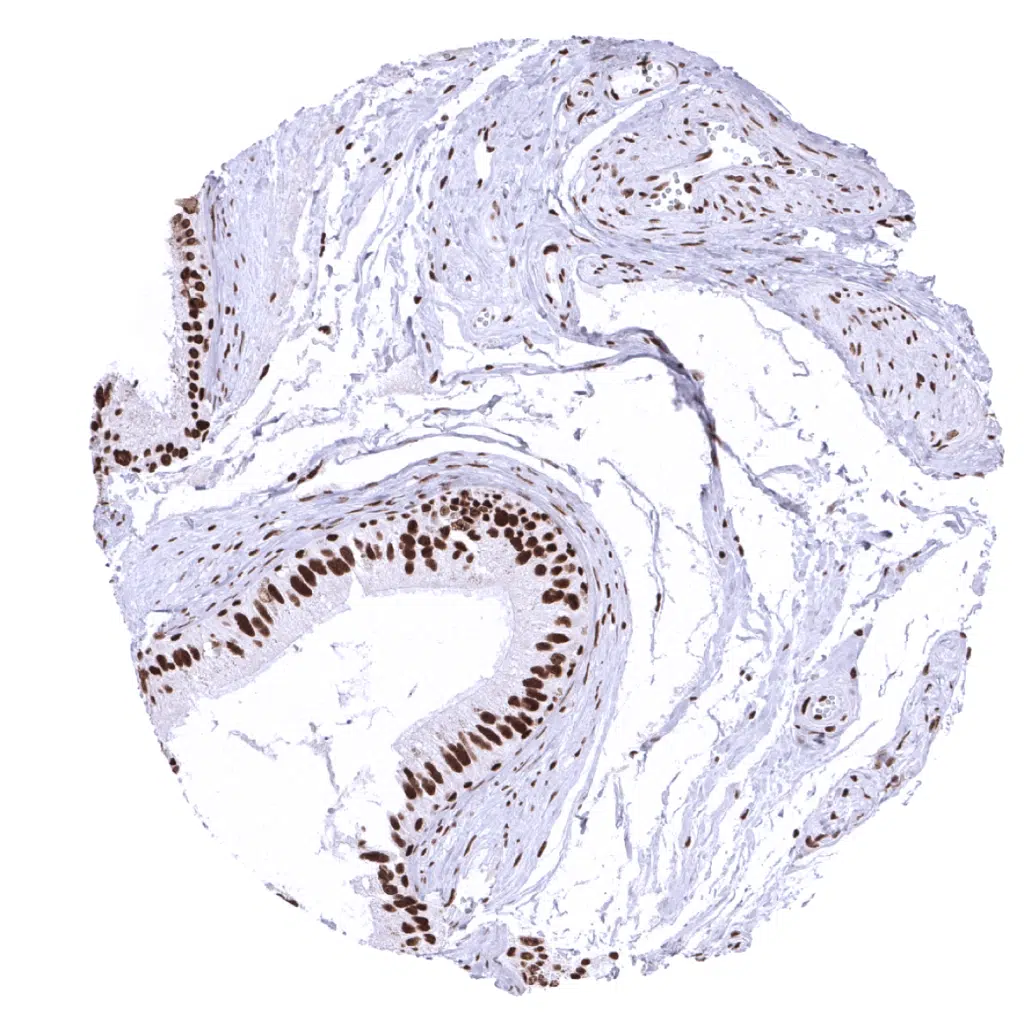

Rectum, mucosa – In the colon (and rectum) epithelium, the MSH2 staining intensity decreases from the bottom to the top of the crypts.